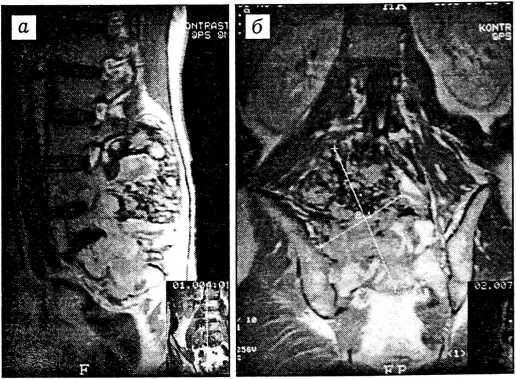

В начале 1993 г. появились боли в пояснице, иррадиирующие в правую ногу, затем припухлость. В феврале 1994 г. в одной из крупных московских больниц удалена «фиброзная гистиоцитома» мягких тканей поясничной области. Через 3 мес после операции стал отмечать слабость в правой ноге, а в 1996 г. обнаружил рост объемного образования в области послеоперационного рубца. Лечился по совету «целителей» мочой (локально и внутрь) без эффекта. Обратился к врачу только в июне 1998 г. В той же больнице проведена магнитно-резонансная томография в режимах СПИН- и МУЛЬТИ-эхо в сагиттальной и аксиальной проекциях; толщина срезов 4 и 5 мм (рис. 1).

Рис. 1. Магнитно-резонансная томограмма больного Б. в сагиттальной (а) и аксиальной (б) проекциях; толщина срезов 4 и 5 мм.

В области L5 и S1-2 позвонков определяется многоузловое образование однородной структуры, растущее вправо и кзади и инфильтрирующее мягкие ткани и подвздошную кость.

В области L5 и S1-2 позвонков обнаружено многоузловое образование однородной структуры, растущее вправо и кзади, инфильтрируя мягкие ткани и подвздошную кость, изоинтенсивное на Т2- и Т1-взвешенных изображениях (относительно костной структуры позвонков). Размеры патологического образования 11,8 × 8,7 см. На этом уровне спинномозговой канал резко сужен — до 1/3 просвета. При контрастировании (20 мл магневиста внутривенно) отмечено незначительное диффузное накопление препарата в объемном образовании. Заключение: опухолевидное образование L5 и S1-2 позвонков с прорастанием в мягкие ткани и подвздошную кость. При биопсии образования получено заключение: «злокачественная фиброзная гистиоцитома». Учитывая большую распространенность рецидивного очага и его локализацию, больного планировали выписать под наблюдение районного онколога, но после консультации проф. А.Н. Махсона он был госпитализирован в больницу № 62.